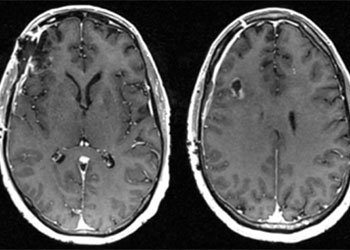

Pre-op

This is a 56-year-old man with a history of COPD and asthma who presented with a syncopal event and one week of retro-orbital headaches, blurry vision, and personality changes including apathy and disinhibition. He had a 40- pack-year smoking history but no prior malignancy. The exam revealed a pronator dri on the le upper extremity. MRI brain demonstrated 2 large right frontal heterogeneously enhancing masses with vasogenic edema causing midline shi and subfalcine herniation. The largest lesion was 3.9 x 4.0 cm on the inferior/sub frontal cortical surface, while the other was 3.0 x 2.7 cm in the superior subcortical frontal lobe. Further imaging showed a mediastinal mass suspicious for malignancy. He was started on Decadron for edema and Keppra for seizure prophylaxis.